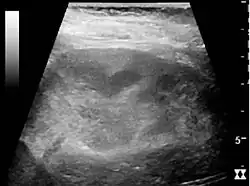

Хронический пиелонефрит с уменьшением размера почек и очаговым истончением кортикального слоя. Измерение длины почек на ультразвуковом изображении показано знаком «+» и пунктирной линией.[4]